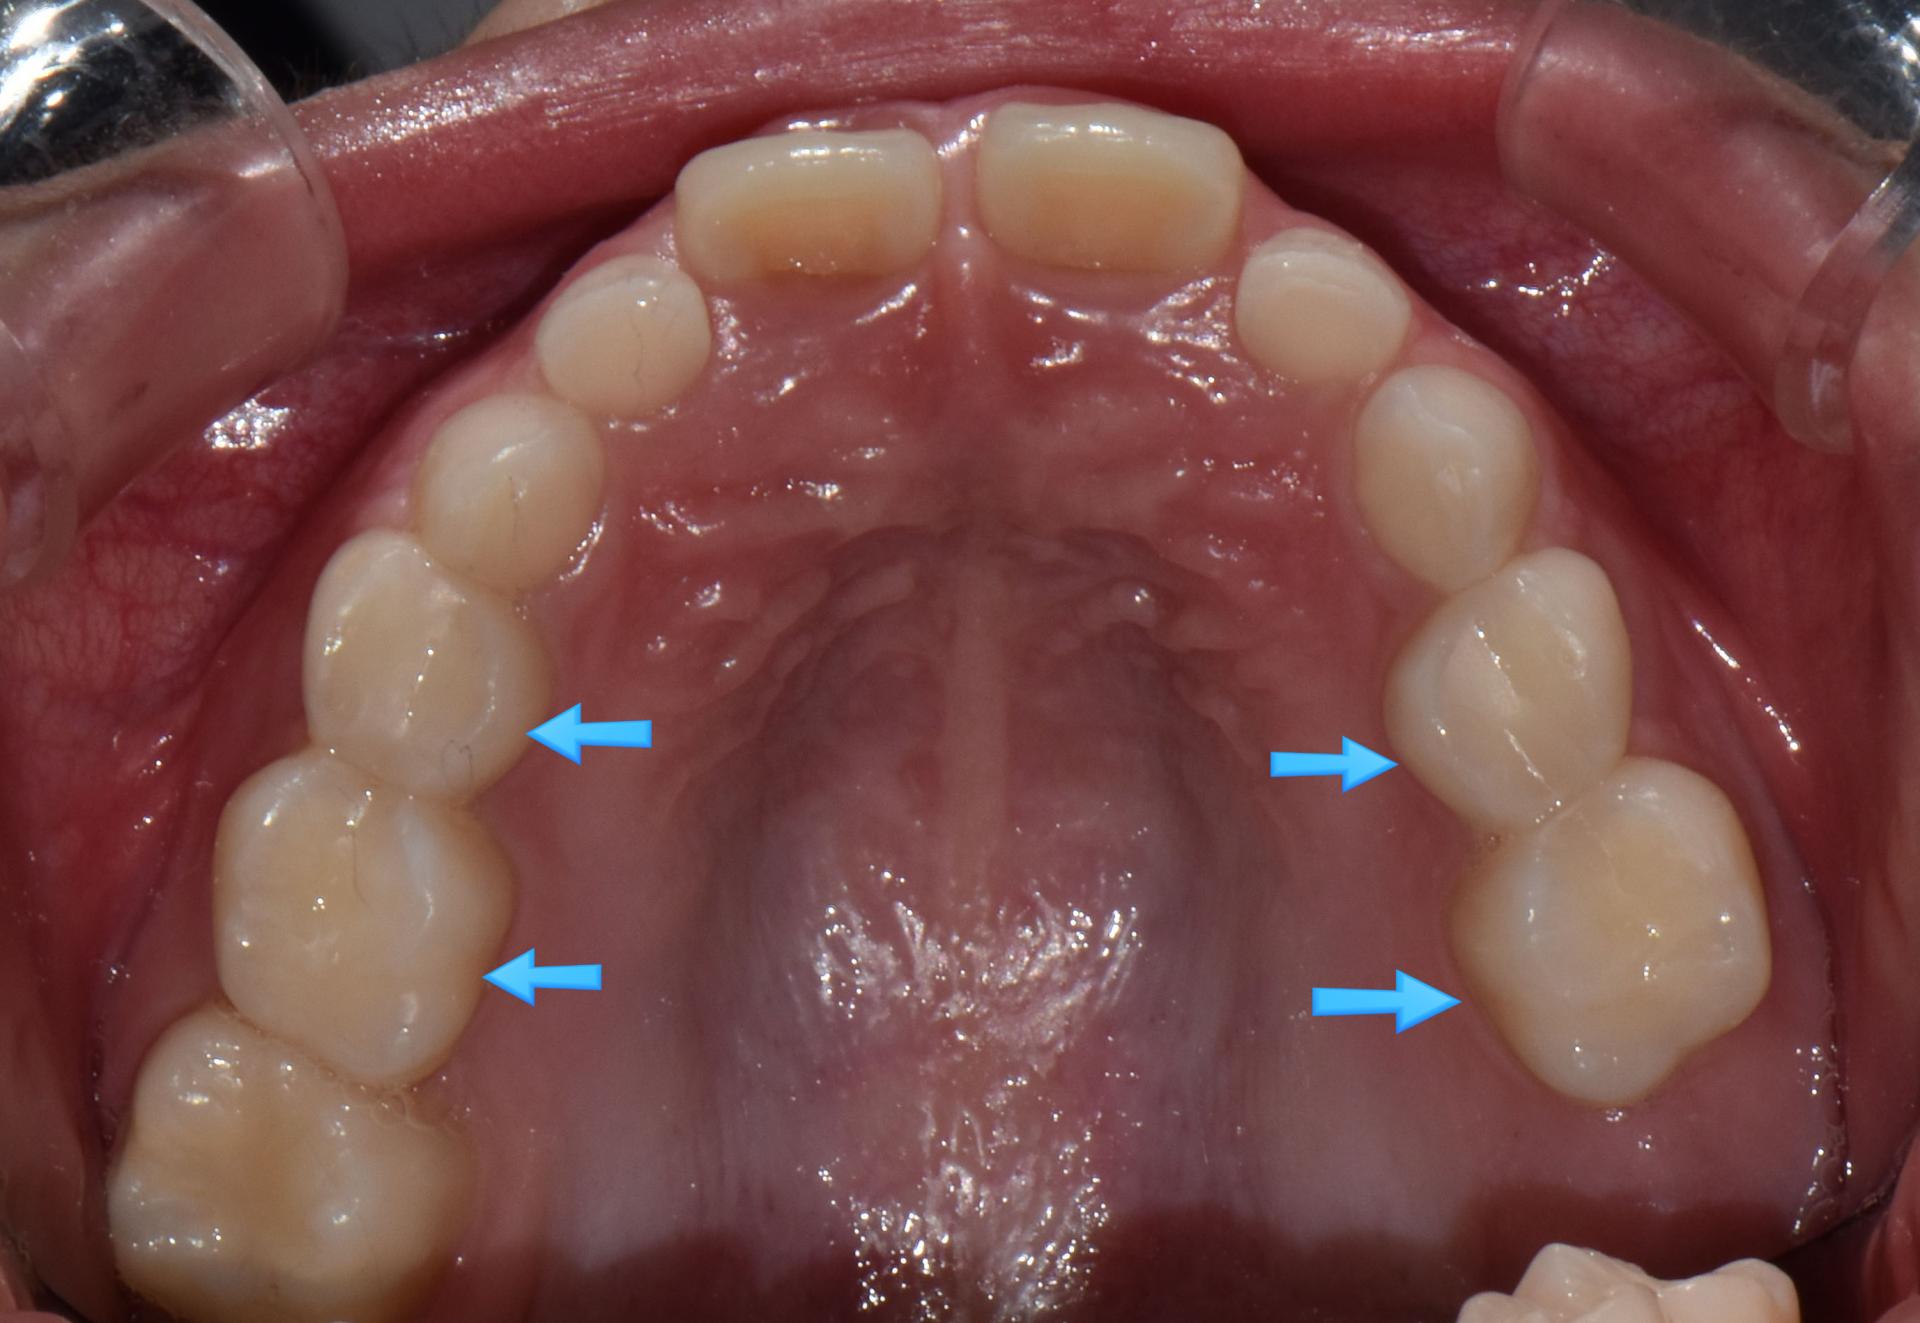

치아 사이충치를 레진으로 8개 치료, 아래 어금니 하나는 지르코니아 크라운으로 치료한 제 큰아이 입니다. (아이에게 동의를 구하고 올립니다.ㅎㅎ)

저희 큰 딸은 유치를 모두 수면치료로 치료한 후 , 지금까지 관리 잘하며 아무 탈 없이 지내고 있고, 초등학생이 되어 유치 뒤로 영구치가 4개 났는데 역시 충치가 생겨^^; 다행히 어린시절 힘든 치과치료의 기억이 없어 큰 치과 트라우마 없이 수월하게 웃음가스 만으로 치료 잘 해주었답니다. 지금은 대부분의 유치를 잘 뺴고 영구치로 예쁘게 교환했습니다.